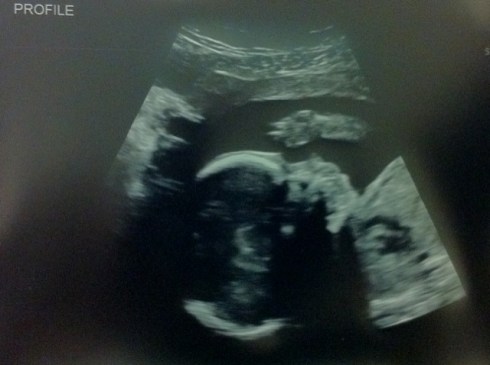

We were at the absolute last day of the 22nd week, though the size of my uterus and the length of our girl measures closer to 24 weeks–she’s already over a pound! Our first view was of the inside of heart, and we could see all four chambers beating, the picture was so precise that we could make out individual chordae tendineae (the “heart strings”). The scan took us through the heart and it’s major vessels (no tetralogy or transposition–two major congenital heart defects–for this kid!), the brain and spine, the kidneys, the limbs, etc. We’ve seen our girl head to toe!